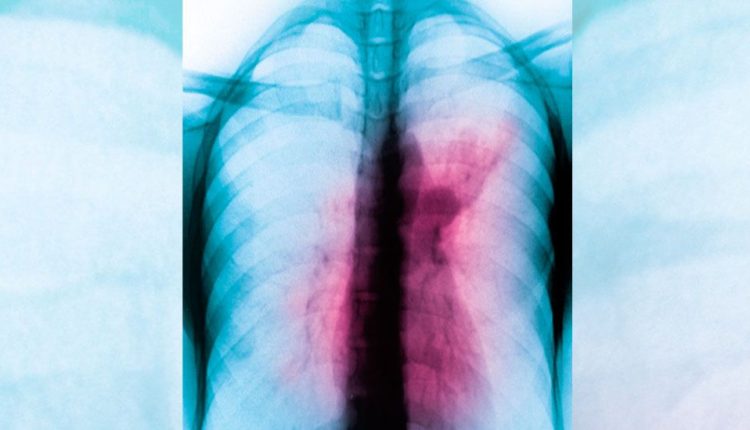

TB is a bacterial infection, spread through inhaling tiny droplets from the coughs or sneezes of an infected person.

It is a serious condition, but can be cured with proper treatment.